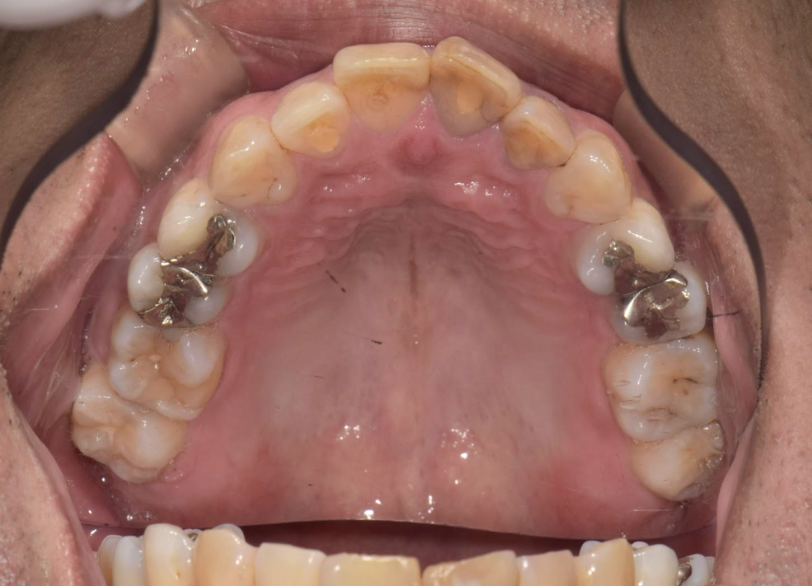

| 診断 | 失活による歯の黒色変化 | ||

| 処置内容 (または主訴) | 失活歯に対するウオーキングブリーチ | ||